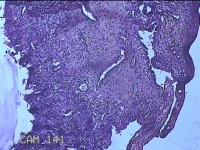

性别

女

年龄

43岁

临床诊断

异常子宫出血

一般病史

月经不规则2年余,发现宫颈赘生物近1年,活检外口可见多个赘生物。

标本名称

宫颈内容物

大体所见

灰白粉红色不规则碎组织1.2x0.8x0.3cm一堆。

图4